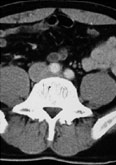

症例6

67歳 男性

【主 訴】

検診異常

【起始・経過】

平成15年より腹部大動脈瘤を指摘。

平成18年1月CTにてφ5cm大のAAAを認め7月当院紹介受診。

【既往歴】

56歳 AMI→PCI

64歳 Rectal Ca→ope

高血圧(+) 糖尿病(−) 喫煙歴(15本×30年)

【治療計画】

Cook Zenith AAA stent graft